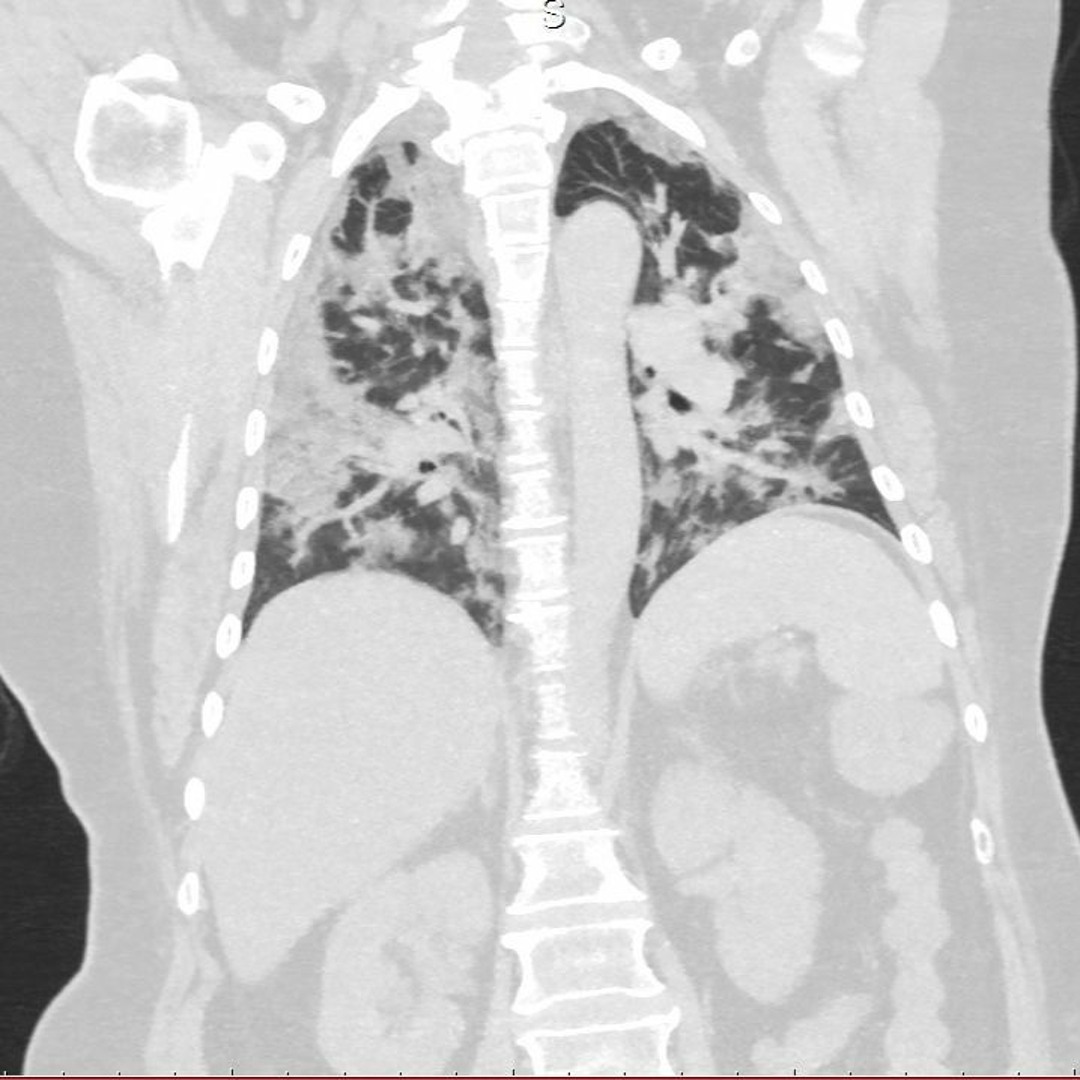

Поражение Легких При Коронавирусе Фото Рентгена

Поражение Легких При Коронавирусе Фото Рентгена 111 фото